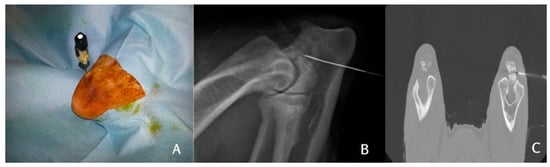

One hour after the harvesting of bone marrow, the dogs were re-anaesthetised with propofol (Propovet, Zoetis, Rome, Italy) (5 mg/kg) and the anaesthesia maintained with isoflurane (Iso-vet, Piramal Clinical Care Spa, Italy) and oxygen. In three of the dogs (n = 3), BMMCs were administered under C-arm fluoroscopy, whereas in three other dogs (n = 3), BMMCs were administered under CT-guided injection. The BMMCs were suspended in 1 mL of fibrinogen and injected using a 22-gauge spinal needle directly inserted into the ossification centre between the anconeal process and the olecranon (Figure 2).

Figure 2.

Injection of the stem cells into the ossification centre. The spinal needle is inserted into the anconeal process (A) and an X-ray (B) or a CT (C) is performed to verify the position of the needle. The stem cells are injected after correct positioning is verified.

Immediately after the injection of BMMCs + fibrinogen, 0.3 mL of thrombin was injected through the same needle to obtain a clot of cells and fibrin glue in the injection site. At the end of the procedure, all dogs were recovered from general anaesthesia.